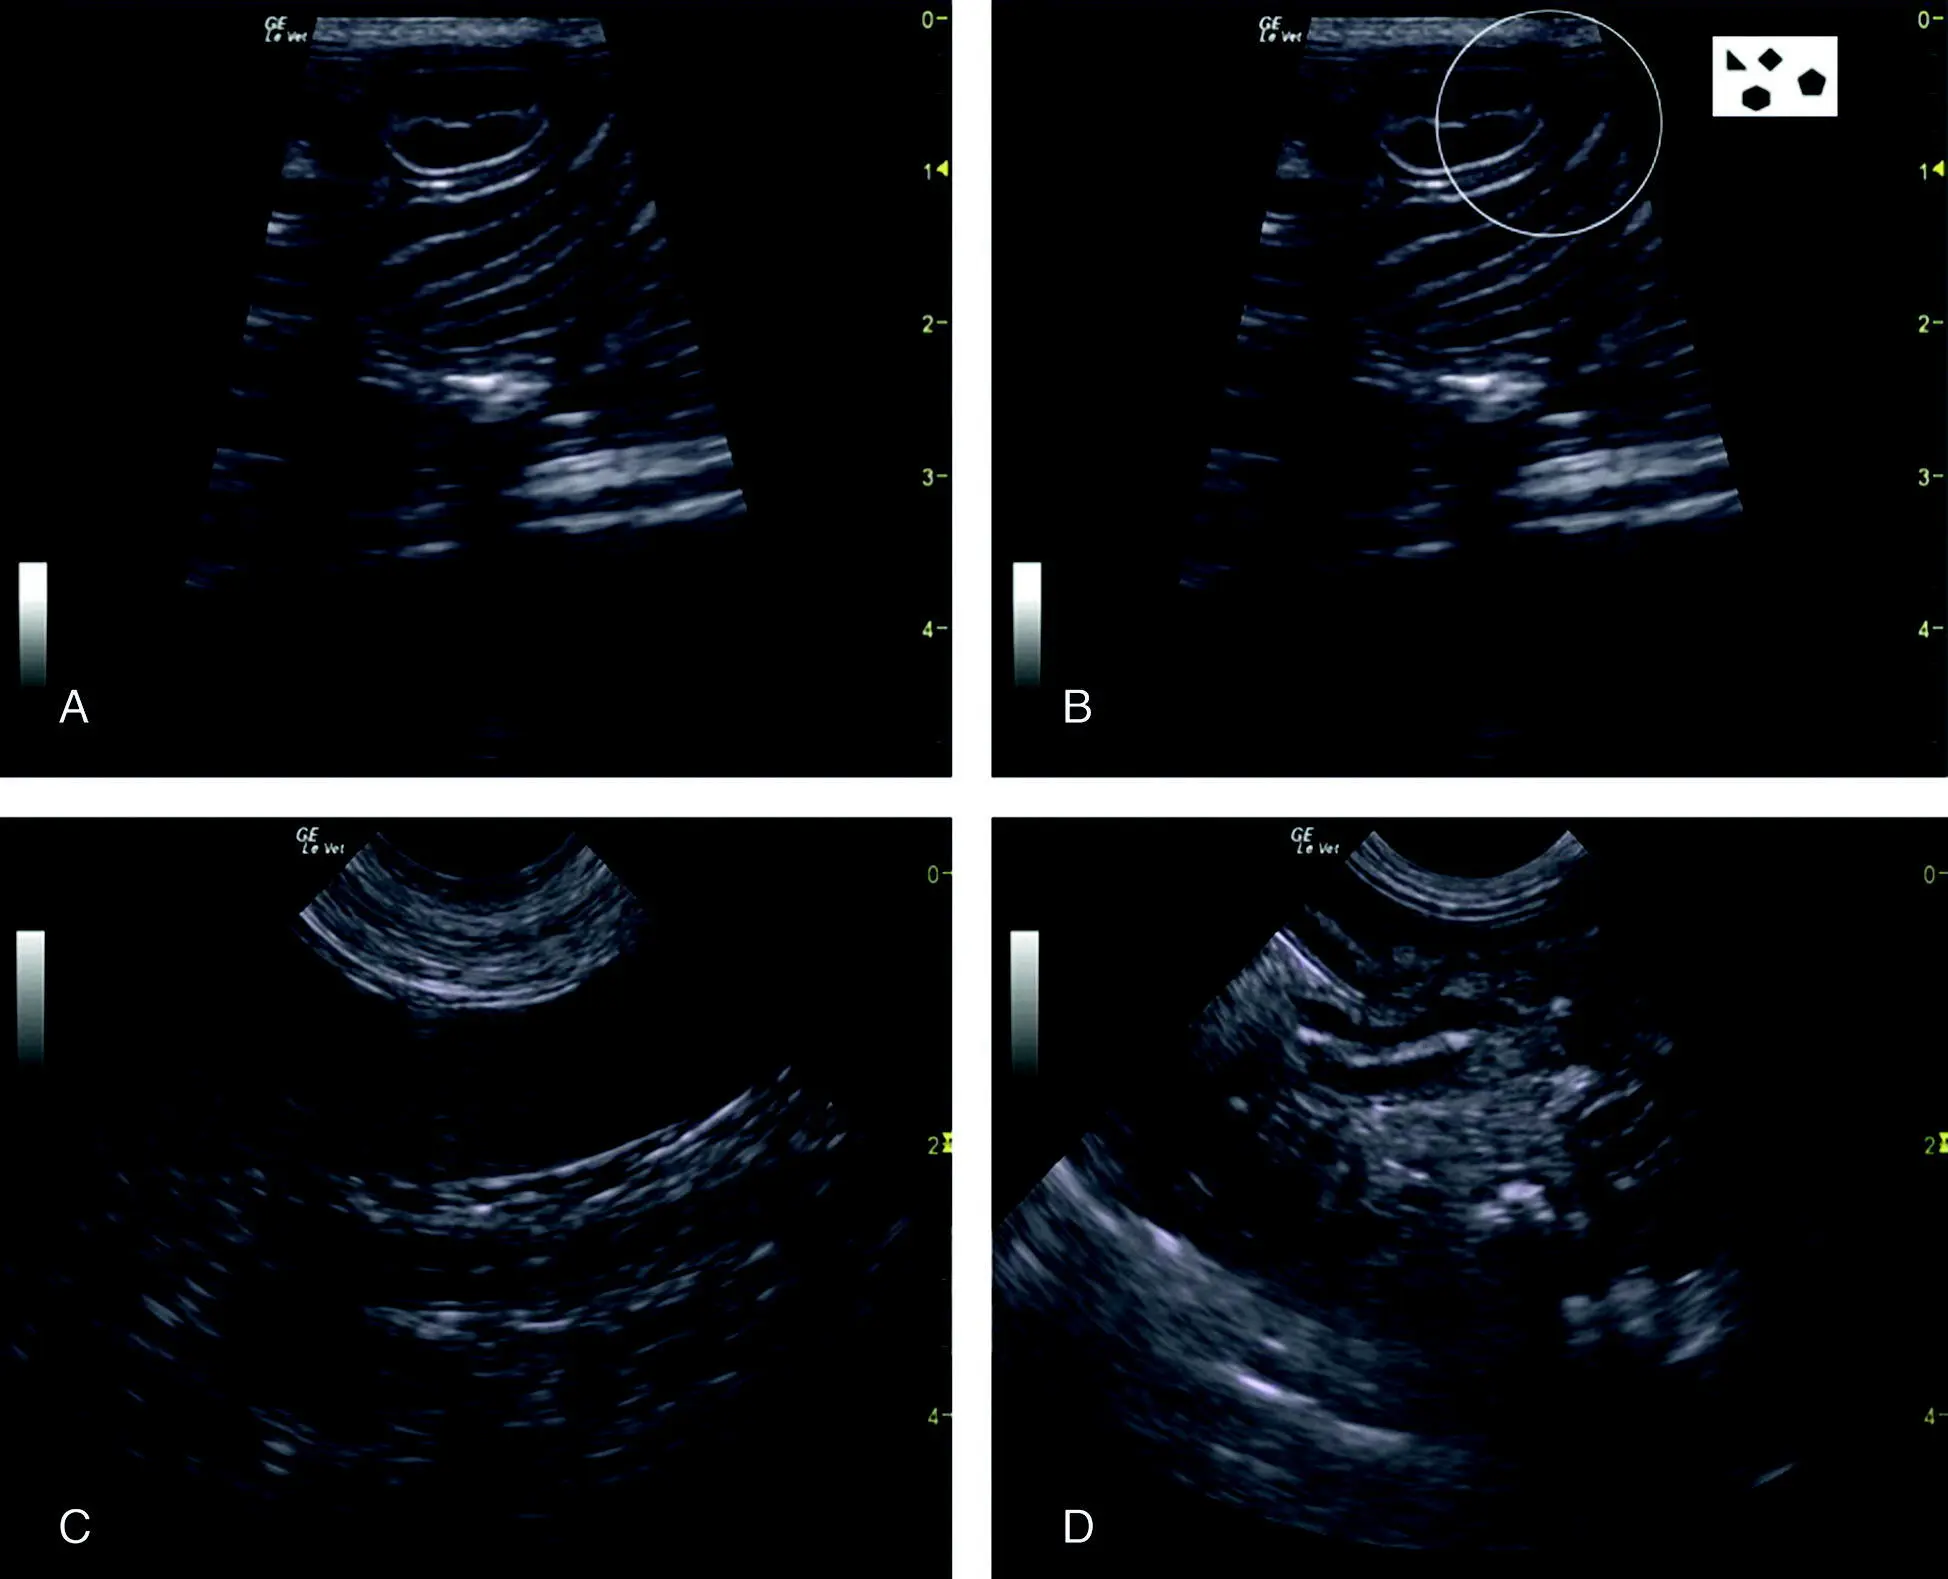

Figure 6.29. Pitfall of the thigh or a mass or other. In (A) and (B) are identical images unlabeled and labeled. The large circle encompasses the region of interest and its suspect origin of being the thigh muscle. The smaller circles are where typically the femoral artery and vein would be located with the patient in lateral recumbency and observing for pulsation or applying color Doppler would be helpful. The image shows how the thigh can push into the urinary bladder or stool in the colon or a caudal abdominal mass and make odd impressions when imaging the CC view with a patient in lateral recumbency. A digital rectal examination as part of a good physical examination with or without more advanced imaging is an ancillary evaluation to increase the probability of being correct. From the still B‐mode image, the exact origin of the circled structure may be unclear. UB, urinary bladder.

Source: Reproduced with permission of Dr Gregory Lisciandro, Hill Country Veterinary Specialists and FASTVet.com, Spicewood, TX.